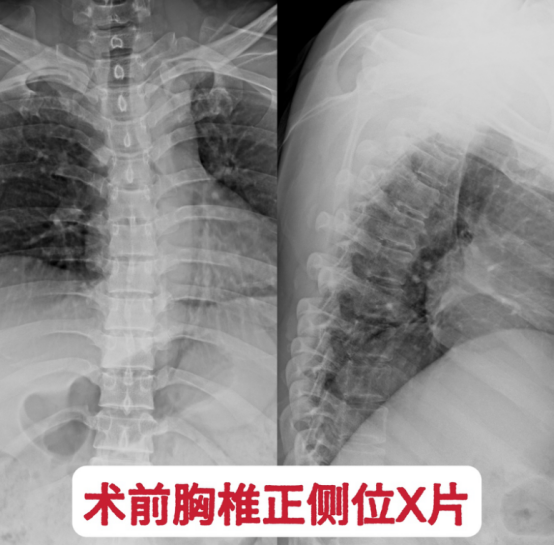

图1. 术前胸椎正侧位x片。